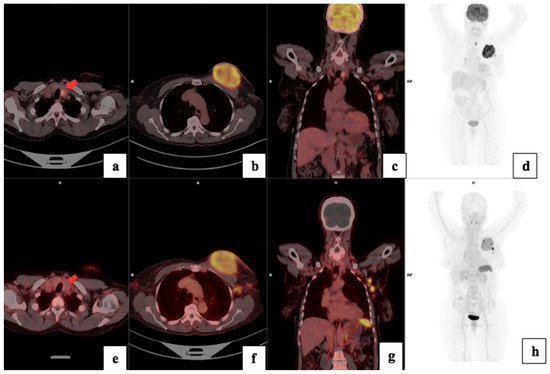

3.5. Treatment Response